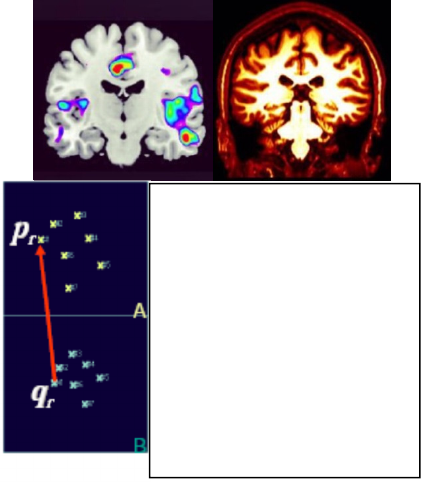

MRI, which indicates brain activity. Figure 2 shows

the vertical MRI scanning; the future work of

(Hughes, 2012) is how to combine the various types

of images into one common format.

Figure 2: Vertical MRI scanning.

The similarities between fMRI and DTI

modalities include the study of anomaly in WM and

deficits in the size of the corpus callosum (the white

crescent in figure 2.). (Lynn, et al., 2014) have been

supported the hypothesis that the disruption of the

corpus callosum constitutes a major risk factor for

developing autism, resulting in the difficulties that

many autistic people have with words and social

interaction. Unfortunately, to diagnose the

Figure 3 illustrates the concept of spatial

transformation that maps from arbitrary point P in

fMRI image to homologous point Q in DTI image.

Figure 3: Image registration finds a spatial transform

mapping one image into another.